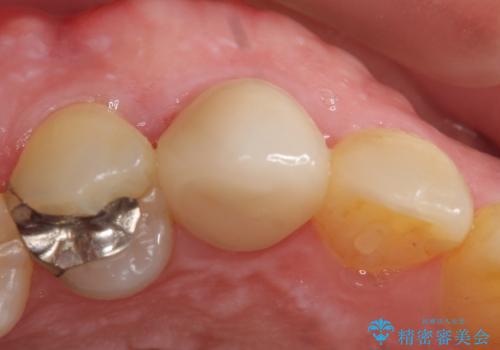

- 他院にて根管治療を行ったが疼きが治まらないため、当院にいらっしゃった方の症例です。

再根管治療を行い症状が治まったのを確認後、オールセラミッククラウン(スペシャル)による補綴を行いました。

- オールセラミッククラウン(スペシャル)…¥130,000、仮歯…¥10,000、ファイバーコア…¥20,000、精密根管治療費別途費用は治療当時の料金となります